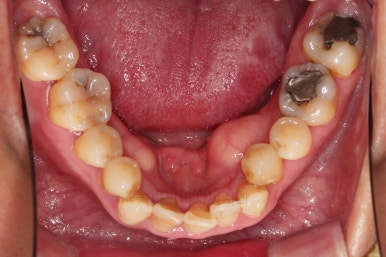

5. 치료과정 및 경과

본격적인 부산구순구개열교정 치료 전에 필요한 부위의 충치치료를 진행합니다.

충치치료에서도 구순구개열 환자분들은 특별한 주의가 필요한 경우가 많습니다.

위아래 장치를 부착했습니다.

초기 단계의 주안점은 아랫니와 악궁과 어울리는 윗니 악궁의 형태를 만들어 주는 것이고요.

악궁확장장치를 사용하지 않은만큼 철사의 형태를 잘 잡아가면서 악궁 형태를 개선시킵니다.

교정 10개월째인데, 악궁형태 많이 좋아졌고, 가지런한 느낌도 많이 좋아졌습니다.